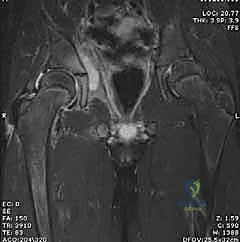

- الرنين المغناطيسي (MRI): يتم اللجوء إليه إذا كان هناك اشتباه في وجود التهاب عظم ونقي (Osteomyelitis) مصاحب، أو خراج في العضلات المحيطة، ولكنه يتطلب تزليج الطفل (تخدير) ويستغرق وقتاً.